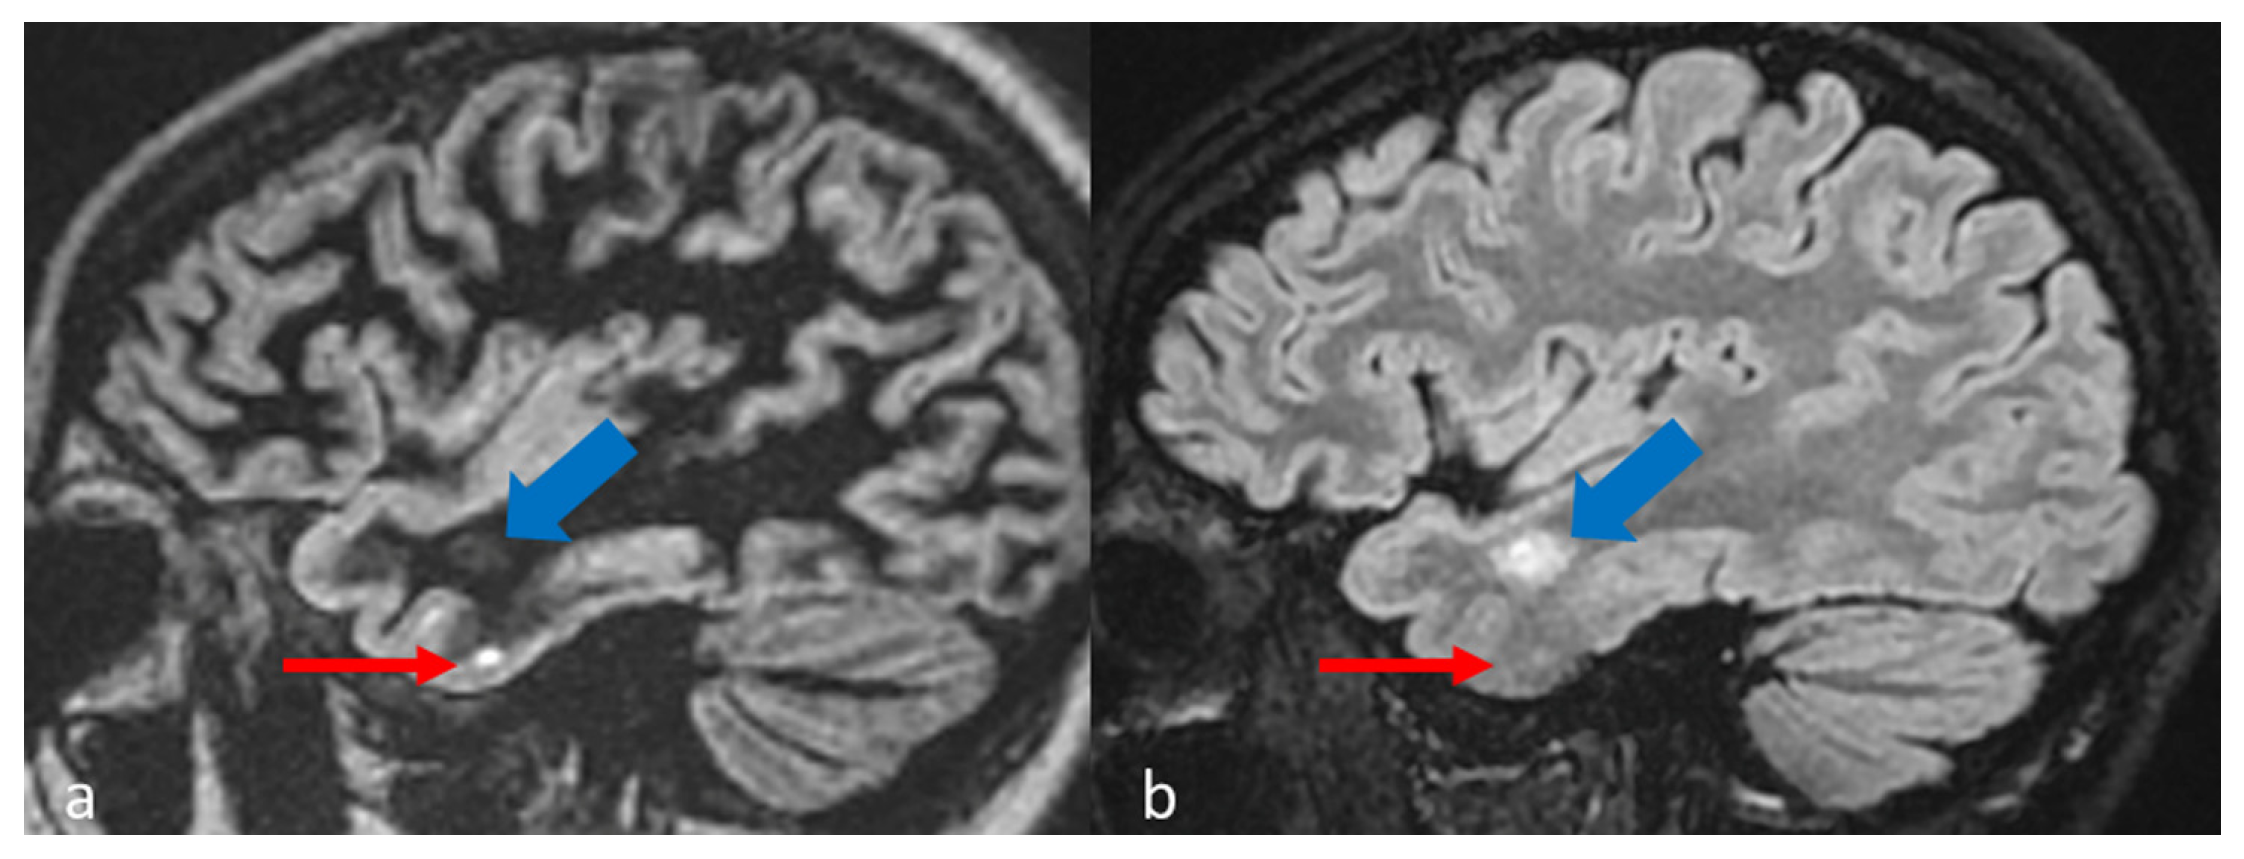

| In MS protocol, attention has to be paid to perform DIR before contrast-administration, as post-contrast DIR may suppress active subcortical lesions. |